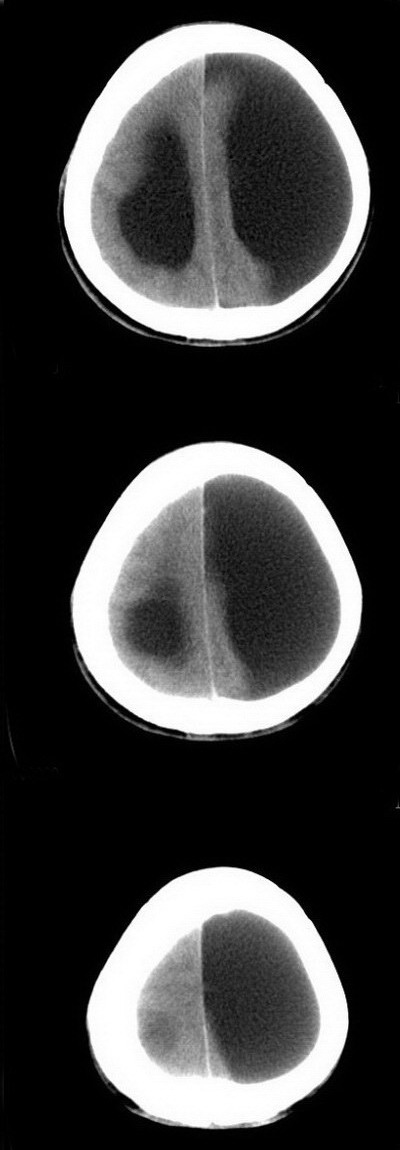

标题: CT16833:F34Y,左侧积水型无脑畸形?请指教. [打印本页]

标题: CT16833:F34Y,左侧积水型无脑畸形?请指教.

女.34.自幼右下肢跛行.智力正常,未发现其它不适。

本例视间隔缺如,基底灰质核团移位,左侧大脑实质较多,能活到这么大还智力正常,多考虑大脑发育不良伴脑积水,积水型无脑畸形一般实质较少而且活不大,智力低下

标题: 左侧脑裂畸形

左侧脑裂畸形(完全型、分离型)。